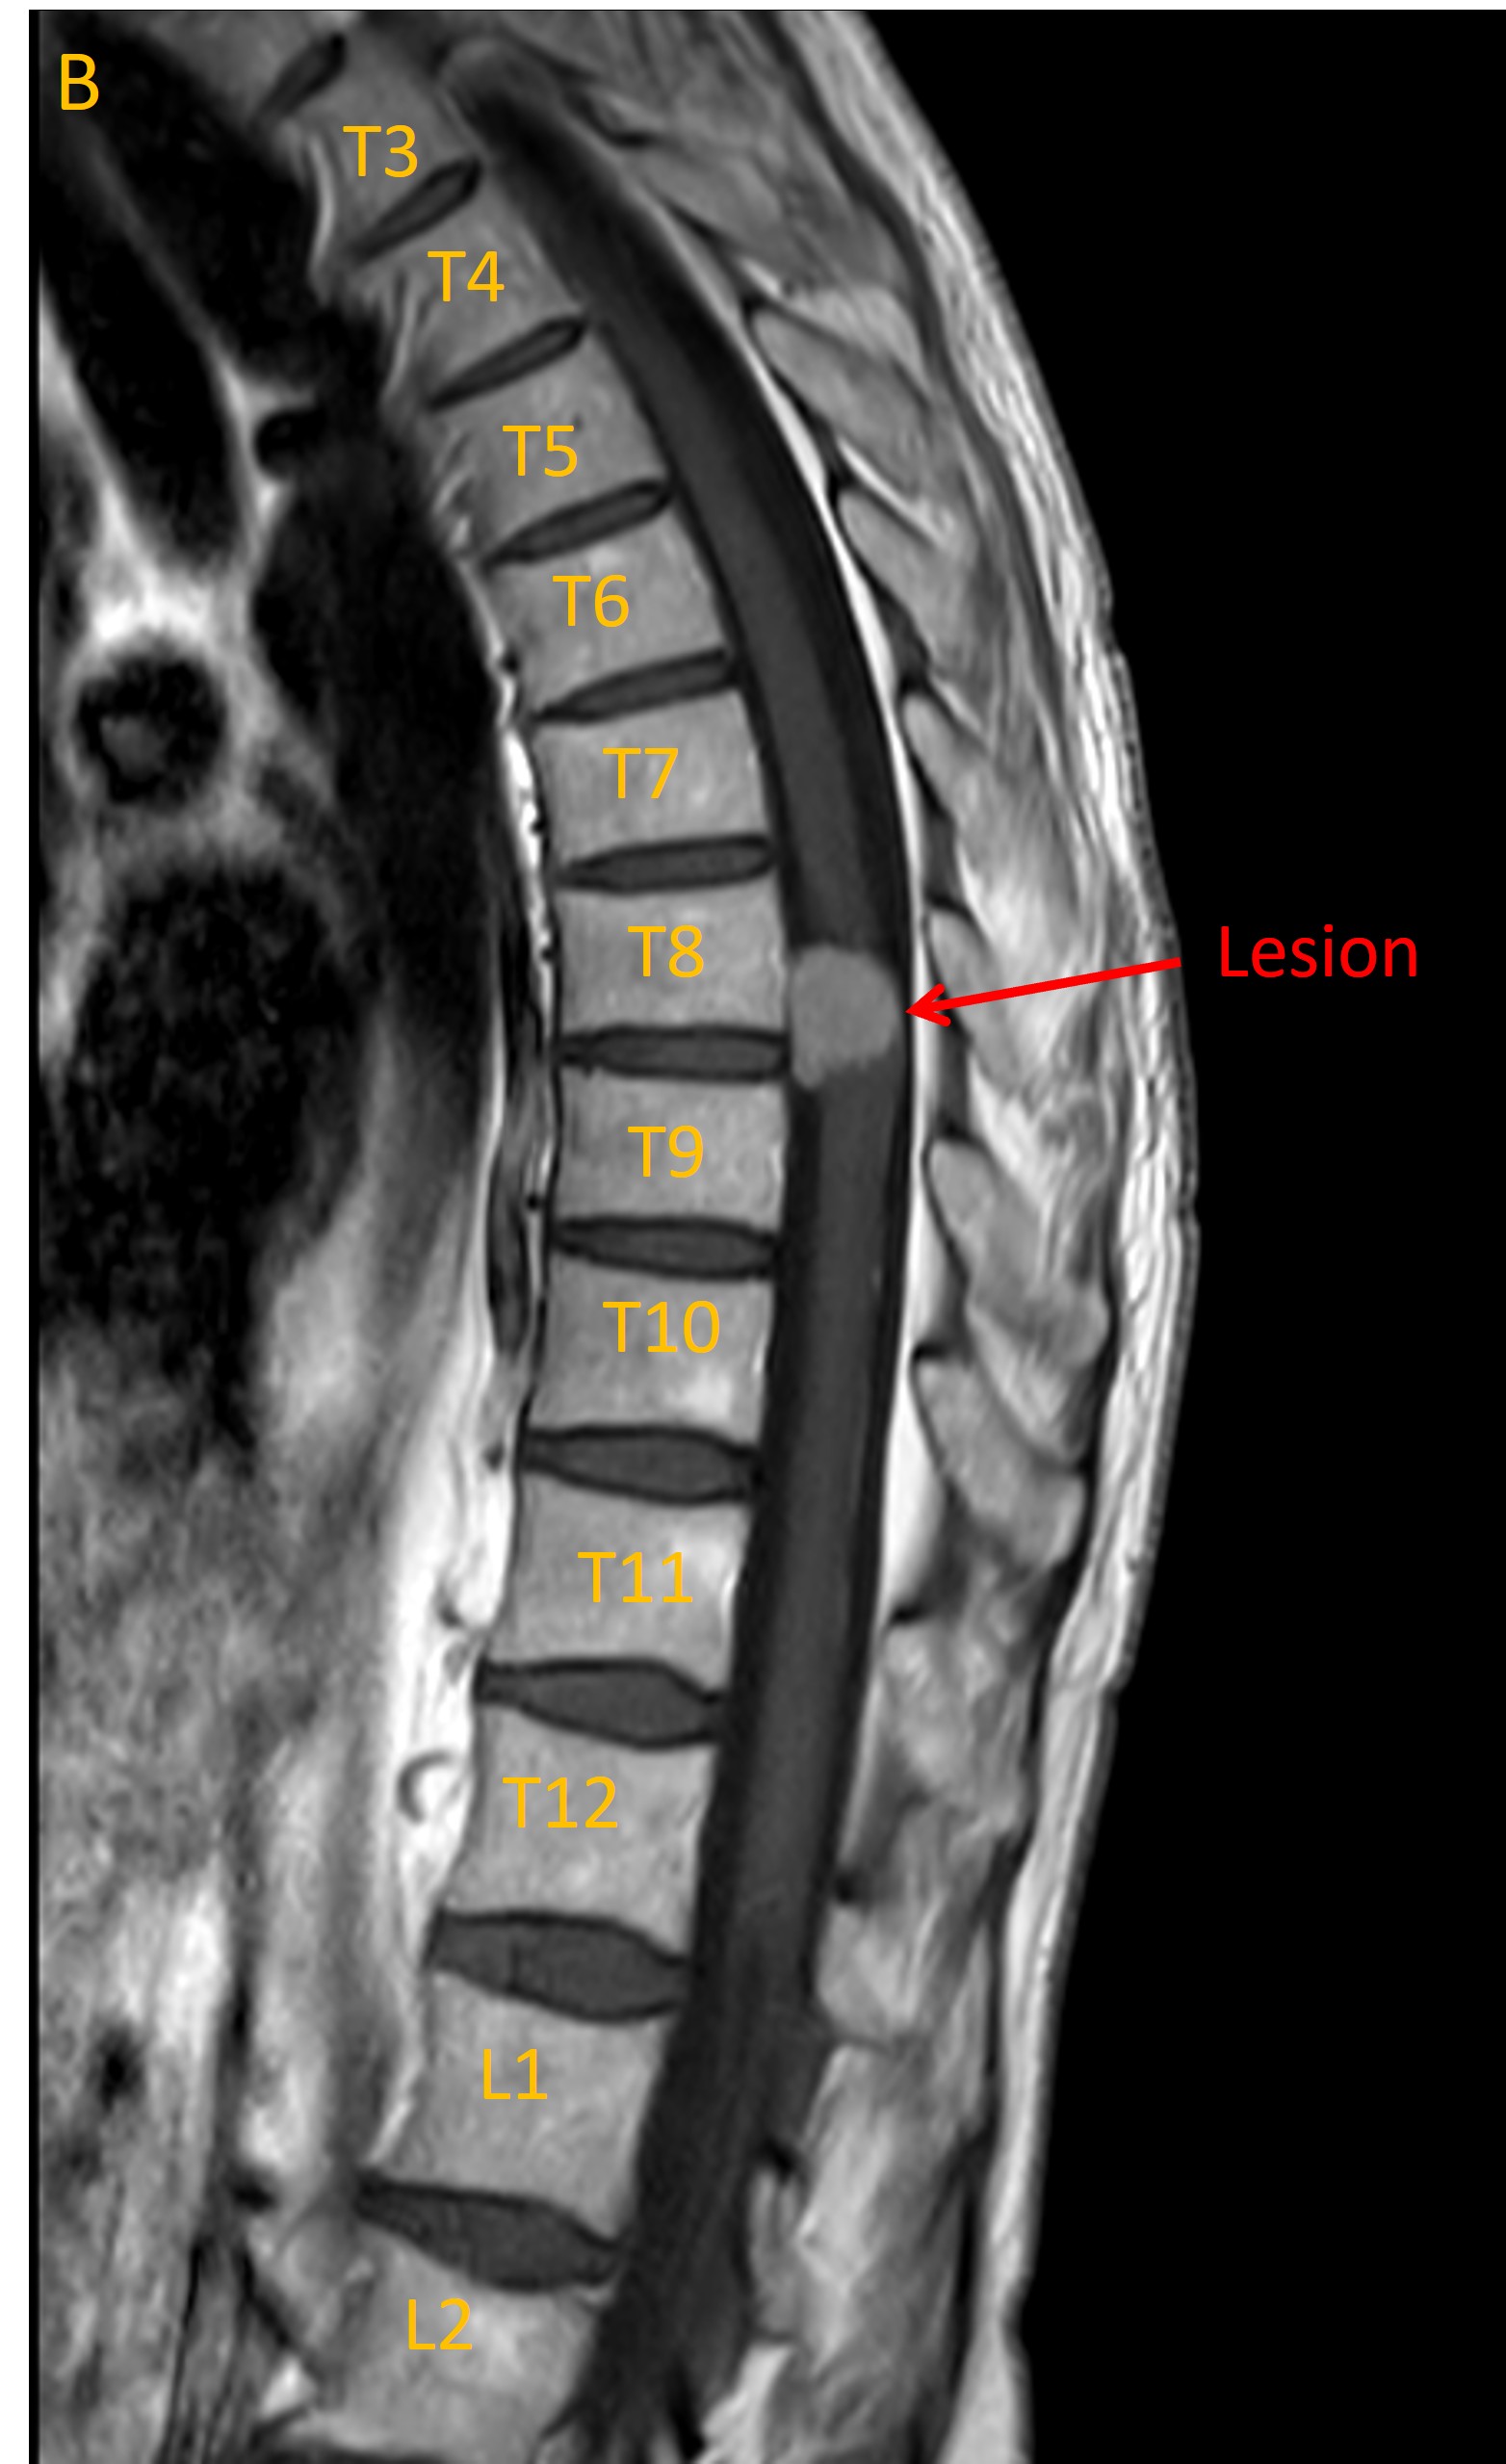

An MRI identified a lesion at T8/9 growing from the meningeal space (Image A, sagittal T2 MRI). This had homogenous contrast enhancement (B, T1 MRI with contrast). There was evidence of lateral displacement of the spinal cord (C, axial MRI).

Sagittal T2

Imaging was consistent with a meningioma. Reassuringly there was no evidence of metastatic disease on body imaging.